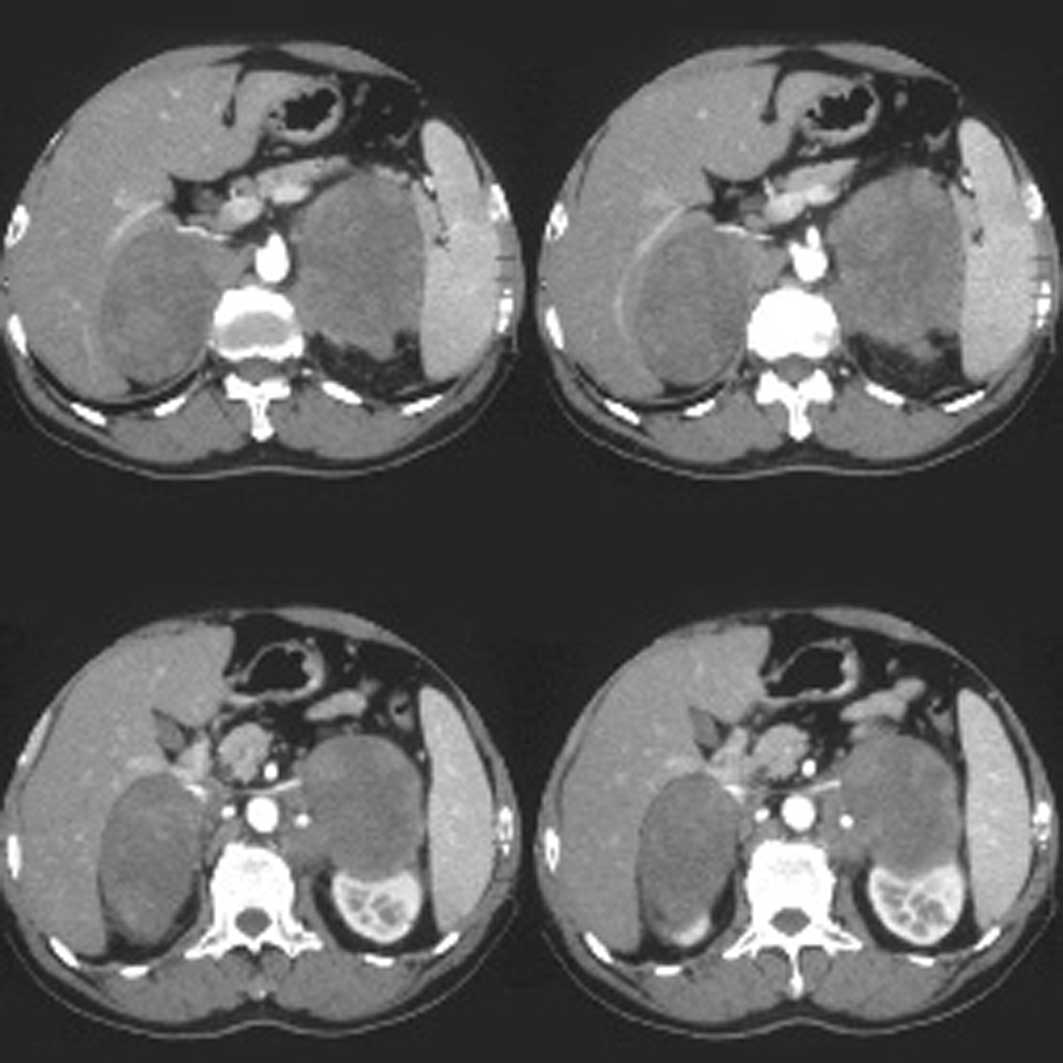

Лимфома яичка диагностика - фото презентация